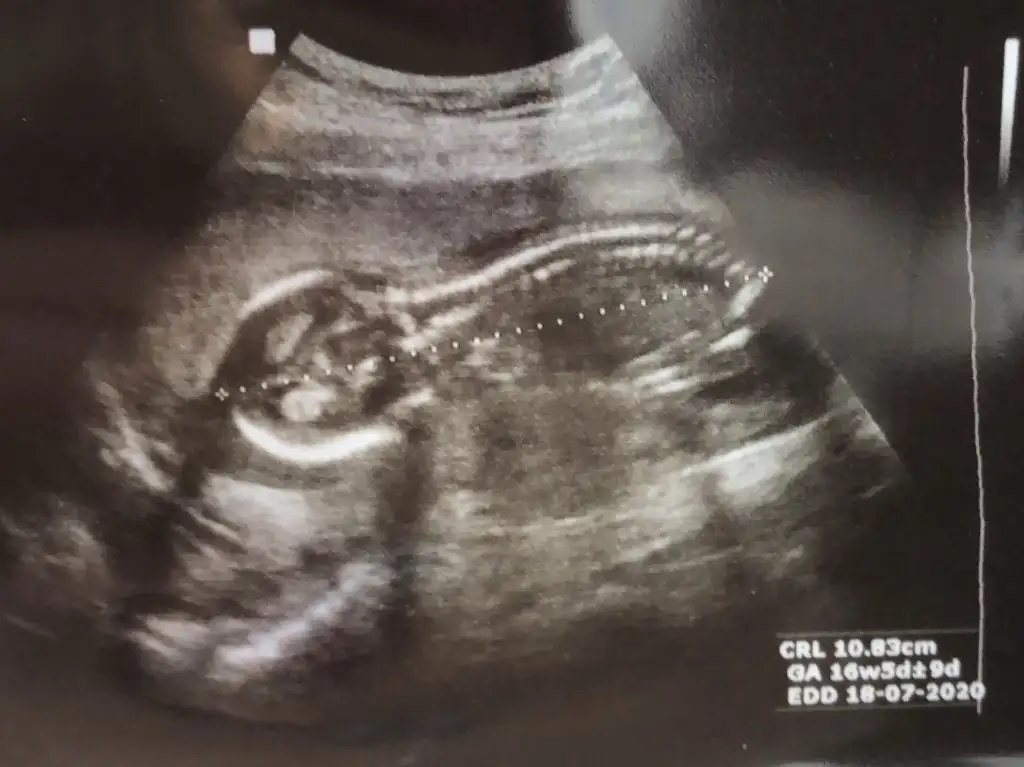

Erkek gibiIkra meyra merhaba 12+2 başka ulstrasyon görüntüsü olursa atın demiştiniz ama bu seferki böyle bir çekim verdi drumuz.teşekkürler

Malesef sadece bunu verdi. Çok teşekkürler tahminiz içinBaşka usg varmı teyit edim

Kız gibi kafasıBugün doktora gittik ama yüzüstü yatıyordu bir şey göremedik :))) siz keseye bakıp erkek, 12. Haftaya bakarak kız demiştiniz. Şimdi 17. Haftadayız:) ben erkek hissediyorum dedim doktor bence tam tersi sanki dedisizce ne olabilir Ikra meyra

12 de Kız tahmin etmiştim hale kız diyorumBugün doktora gittik ama yüzüstü yatıyordu bir şey göremedik :))) siz keseye bakıp erkek, 12. Haftaya bakarak kız demiştiniz. Şimdi 17. Haftadayız:) ben erkek hissediyorum dedim doktor bence tam tersi sanki dedisizce ne olabilir Ikra meyra

12 de Kız tahmin etmiştim hale kız diyorum